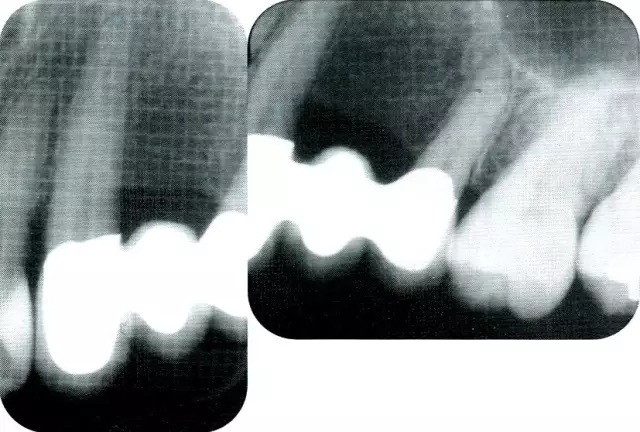

640.webp (14).jpg

▲圖8-9  最終修復(fù)體戴上時的x片,可確認(rèn)尖牙近遠(yuǎn)中部的牙槽骨高度相同。

640.webp (15).jpg

▲圖8-10  術(shù)后11年的x片。術(shù)后的骨水平得到了維持。